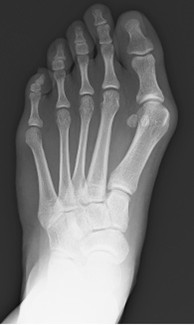

外反母趾の手術的治療

術前レントゲン写真

術後レントゲン写真

外反母趾の写真(左術後、右術前)